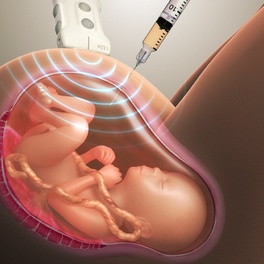

Одним из довольно распространенных методов дородовой диагностики заболеваний у будущего малыша является такая процедура, как кордоцентез плода. Суть манипуляция заключается в заборе крови из пуповины внутриутробного плода с последующим ее исследованием разными методиками. Обычно кровь берется для проведения цитогенетического исследования, но иногда могут быть использованы и другие методы диагностики. Метод может использоваться для выявления определенных генетических нарушений, состояний крови и инфекций. Кордоцентез также может быть использован для доставки крови и лекарств ребенку через пуповину.

Кордоцентез, на каком сроке делают

Если планируется кордоцентез, на каком сроке делают этот анализ, тоже имеет важное значение. Проводить кордоцентез представляется возможным, начиная с 20 недели беременности, но оптимально проводить исследование в сроке 22-25 недель, как и предусмотрено законодательством. Но при наличии показаний его можно провести как раньше, примерно с 18 недель, так и в более поздние сроки, хотя это связано с техническими трудностями.

Кордоцентез, или чрескожный отбор пуповинной крови, является процедурой, которая может использоваться как в диагностических, так и в терапевтических целях. Наиболее распространенными показаниями являются изоиммунизация и неиммунные отеки; менее распространенным является непосредственное введение лекарств плоду. В случаях аутоиммунной тромбоцитопении у новорожденных метод кордоцентеза исторически использовался для диагностики и оценки реакции плода на терапию у матери. Тем не менее, достигнут огромный прогресс в профилактическом лечении этого расстройства у матери с помощью внутривенного введения иммуноглобулина и преднизолона; серийный кордоцентез больше не рекомендуется. Забор крови плода может использоваться для подтверждения того, что количество тромбоцитов плода достаточно высоко для безопасных вагинальных родов у пациенток, желающих избежать кесарева сечения. Кордоцентез и внутриматочная трансфузия до сих пор широко используются в случаях подозрения на анемию плода. Забор крови плода должен быть выполнен для подтверждения диагноза перед внутриутробным переливанием и должен быть сделан в ультразвуковом отделении, или, если плод жизнеспособен, в обстановке, где при необходимости может быть выполнено срочное кесарево сечение.

Марина, здравствуйте. Амниоцентез – это инвазивная диагностика генетической патологии у плода во время беременности, которая проводится в специальном учреждении путем исследования амниотической жидкости. Ее получают путем пункции и получения околоплодных вод с соблюдением всех правил асептики и антисептики под контролем УЗИ. Опасность данного метода врачи объясняют тем, что есть угроза отслойки плаценты, угрозы прерывания беременности, травмы плода, кровотечения, а также инфицирования его. Избежать все это можно только в том случае, если соблюдать сроки выполнения, проводить манипуляцию специалистам высокого уровня квалификации, а также максимально бережно.

Амниоцентез осуществляется только врачами под контролем УЗИ с соблюдением всех правил асептики и антисептики. Исследование лучше всего проводить в месте, где нет плаценты и сосудов, чтобы минимизировать развитие осложнение и снизить их риск. Для безопасности исследования околоплодных вод сегодня помимо специальной иглы существуют и специальные адаптеры, позволяющие строго контролировать глубину, на которую игла проникает в матку. После получения амниотической жидкости в обязательном порядке контролируют состояние плода и плаценты.